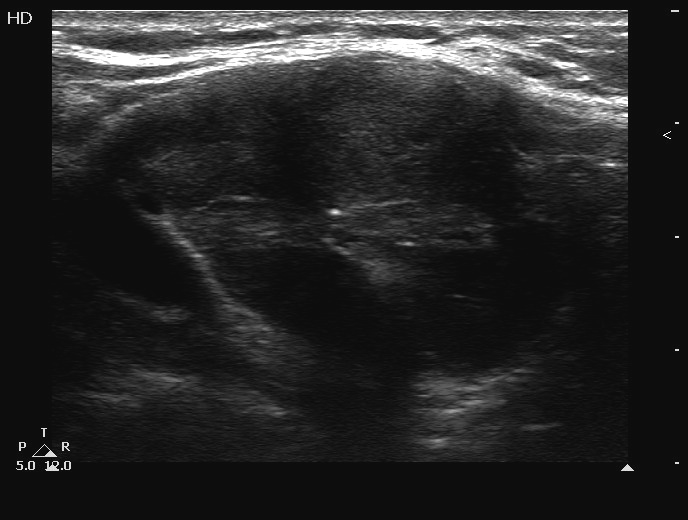

Ultrasonography. The thyroid was echonormal and contained several cystic areas and an echonormal nodule in the right lobe. There was a large, partly echonormal, partly hypoechogenic nodule in the left lobe. This lesion had irregular borders and presented an irregularly increased intranodular vascularization.